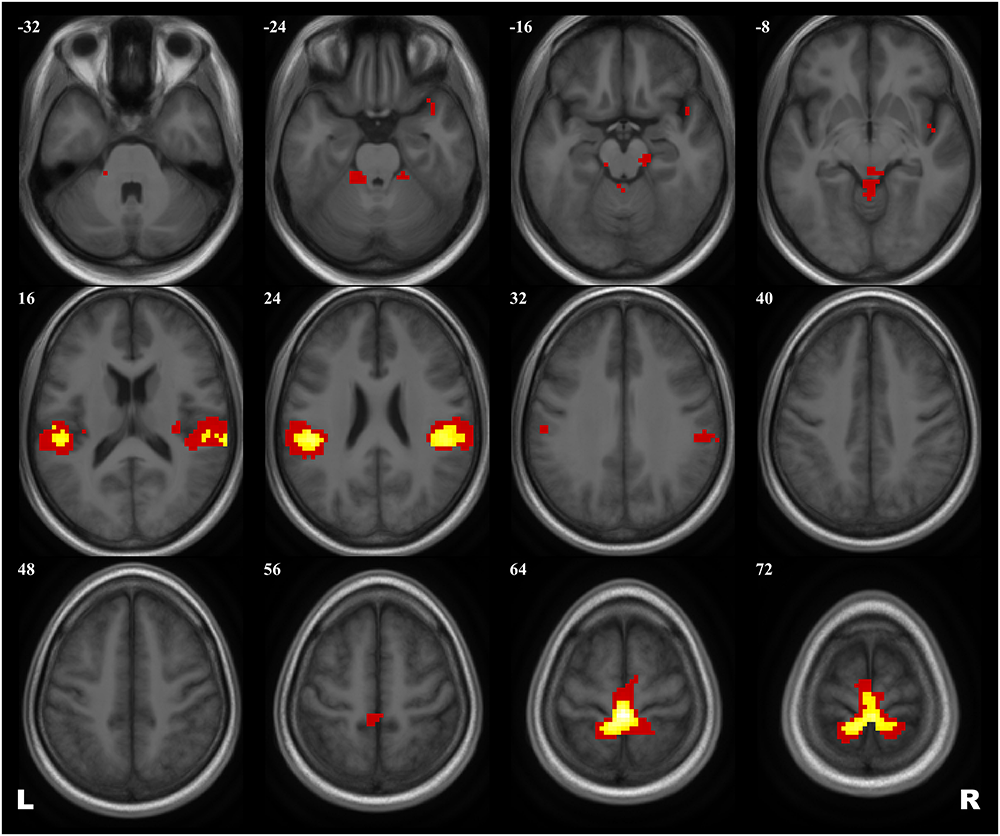

A 2 × 2 ANOVA showed no effect of Group × Scanning session interaction on brain activation evoked by the plantar stimulation paradigm. The aggregated statistical map for both groups revealed an activation pattern that included the primary SMC, the supplementary motor cortex (SMA), extensive regions in operculum bilaterally, and, when applying low statistical thresholds, areas of the right insula and the temporal pole and of the anterior cerebellum (see Figure 2 and Table 3).

FIGURE 2

Group map of the activation elicited by plantar stimulation in all participants (both cosmonauts and healthy controls). Yellow areas depict activation at a reliable statistical threshold (cluster-wise FDR correction, q < 0.05, p < 0.05; voxel-wise cluster-defining threshold, p < 0.001 uncorrected). Activation at a lenient statistical threshold (p < 0.05 uncorrected voxel-wise, k = 5) is shown in red. The statistical images are presented as overlays upon the average structural image of all participants converted to the MNI space.